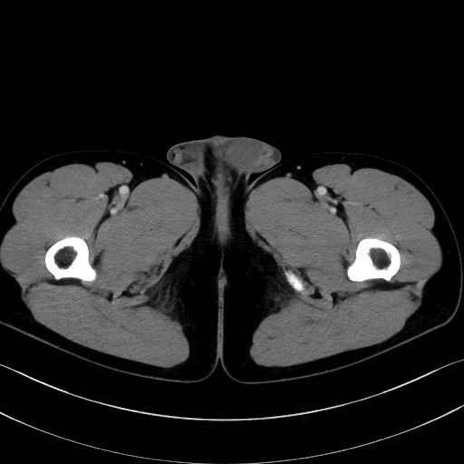

肛門挙筋(levator ani muscle)のCT画像の解剖

肛門挙筋 (Levator ani)

内閉鎖筋 (Obturator internus)